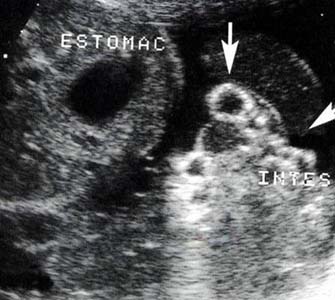

Mesure du DIO